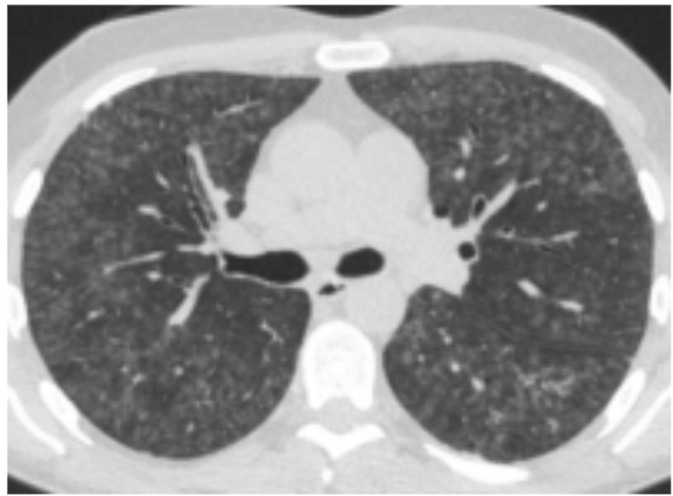

Non-fibrotisk AA

Den typiske HRCT viser diffus matglastegning med involvering af alle lungeafsnit med enkelte sparede lobuli, mosaikattenuering, centrilobulæ re mikronoduli og air trapping (figur 1). Foran dringerne er ofte reversible ved ophør af ekspo nering og med evt. steroidbehandling.

Figur 1. HRCT ved non-fibrotisk allergisk alveoli tis.